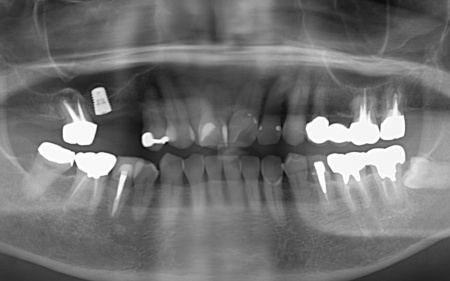

60代女性 歯根が割れて痛む歯を抜いてインプラント治療で噛み合わせを回復した症例

| カウンセリング・診断結果 | 拝見したところ、右上の歯には、欠損部位前後の歯を土台として橋を渡すように連結した被せ物「ブリッジ」が装着されていました。 しかし、土台となっている手前の歯(第2小臼歯)は歯根が割れており、同じく土台となっている奥の歯(第2大臼歯)は歯根の先に膿の袋ができる「根尖病巣(こんせんびょうそう)」が認められます。 さらに、ブリッジ部位の歯茎は腫れ、痛みもあるとのことでした。 かかりつけの歯科医院では、細菌感染を抑える薬を飲んだり、歯を少し削って噛み合わせを調整したりして様子を見ていましたが、口腔内の状態が改善せず、次は抜歯をする必要があると説明を受けたそうです。 また抜歯後に歯を補う方法のひとつにインプラント治療がありますが、患者様の場合は治療に必要な骨量が確保できないため難しいとされ、取り外し式の入れ歯になるとのことでした。 患者様はかかりつけ医からの説明が十分でないと感じていたため、当院にセカンドオピニオンで来院されています。 以上のことから、まずはブリッジ周辺の治療を行ったのち、欠損部を補う治療方法をしっかりと検討する必要があると診断しました。 |

| 行ったご提案 ・治療内容 | 痛みが出ているブリッジ周辺の治療として、ブリッジの土台となっていて、歯根が割れている手前の歯(第2小臼歯)は抜き、根尖病巣を発症している奥の歯(第2大臼歯)は、根管治療を行います。 根管治療とは、感染した神経を取り除いて、歯根内部を清掃・消毒する治療方法のことです。 抜歯と根管治療を行ったあとは、欠損部を補うために、2本のインプラントを埋入する方法を提案しました。 インプラントを埋入するために必要な骨量が足りない場合は、鼻の空洞(上顎洞)の粘膜を少しずつ押し上げて骨を増やす「ソケットリフト」を併用することもお伝えしています。 インプラント治療のメリット インプラント治療のデメリット それぞれの方法について丁寧にお伝えした結果、治療に同意いただきました。 まずは、右上手前の歯(第2小臼歯)を抜きました。 抜歯後は、インプラント治療を行うために、歯を支える骨(歯槽骨)の回復を待つ必要があり、最低でも6ヶ月を要します。 約2ヶ月後、インプラントと骨が結合したことを確認して、右上奥歯2本の仮歯を作製し、手前の歯槽骨が再生するまで経過観察を継続します。 約4ヶ月後、歯槽骨の再生が確認できたため、もう1本のインプラントを埋入しました。 当院のインプラント治療は、施術の安全性と長期的な使用を可能にすることを優先して治療を行うため、通常は抜歯後に歯槽骨の治癒を待ってからインプラントの埋入を行っています。 右上奥歯2本に仮歯が入り、噛み合わせが安定した状態になったため、根尖病巣を発症している右上奥歯の治療を開始します。 また、インプラントに装着する人工歯を作製する前に、歯科医院で歯を白くするオフィスホワイトニング治療を希望されたため、治療期間がやや長くなっています。 最後に、完成した人工歯を装着し、見た目や噛み合わせに問題がないことを確認して、治療を終了しています。 |